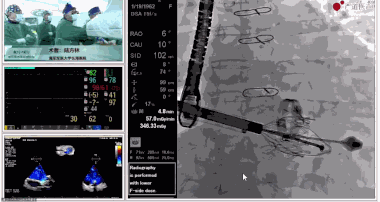

▲瓣膜植入后釋放的過程

▲瓣膜植入后三維超聲影像

▲瓣膜植入后右心室造影

在手術(shù)直播中瓣膜植入過程不到10分鐘,手術(shù)獲得圓滿成功,充分體現(xiàn)徐志云、陸方林團隊技術(shù)精湛,團隊協(xié)作默契及器械的優(yōu)越性。

該例患者返回后當天拔除氣管插管,生命體征穩(wěn)定,恢復良好。此次會議不僅有最前沿的學術(shù)講座,更有3D體驗般的手術(shù)直播,為大家第一視角直觀呈現(xiàn)領(lǐng)域新技術(shù)、新策略、新思路。